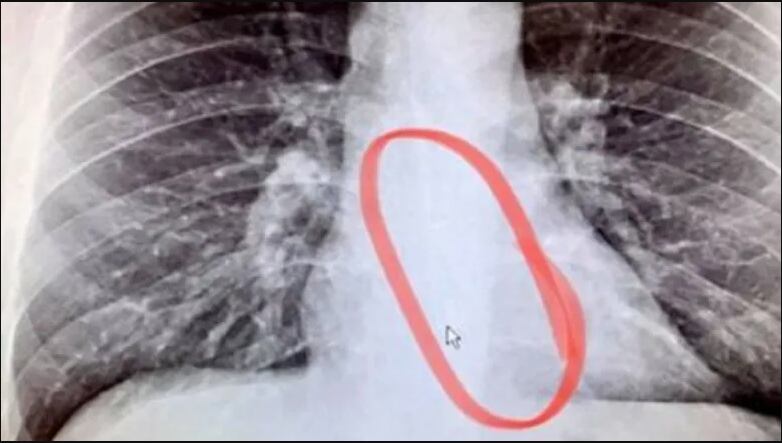

Bellmer, de 27 años, aseguró en su TikTok que gracias a una radiografía confirmó que tenía el AirPod de Apple en su estómago y que afortunadamente luego pudo expulsar de manera natural y sin intervención médica.